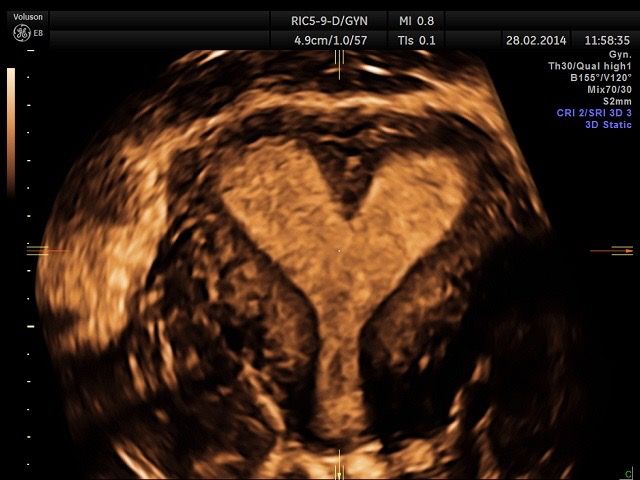

• Visite ed Ecografie Ostetriche: gestione della gravidanza fisiologica, translucenza nucale (membro accreditato ufficialmente), ecografia morfologica e del terzo trimestre